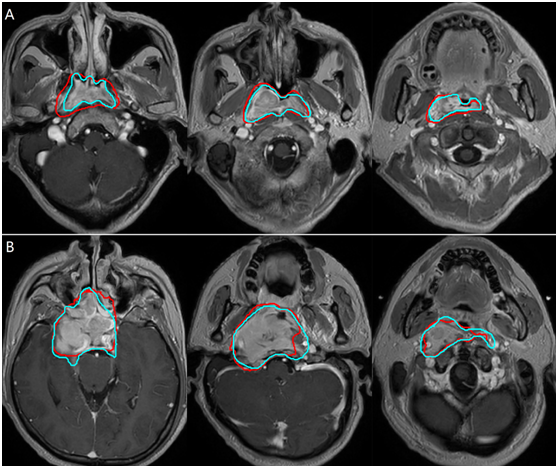

Chinese scientists have realized automated tumor target contouring on magnetic resonance imaging (MRI) pictures of nasopharyngeal carcinoma patients, which is empowered by artificial intelligence (AI) technology and can help improve the efficiency and accuracy in radiation therapy of the tumor. [Photo provided to chinadaily.com.cn]

The AI system scored a 79 percent accuracy rate in tumor target contouring in the research led by Sun Ying, a professor at the cancer center.

In 66 of the 203 research samples, the AI-automated contouring results could be used for radiation therapy planning without any correction, and in other 114 samples, only minor corrections were necessary.